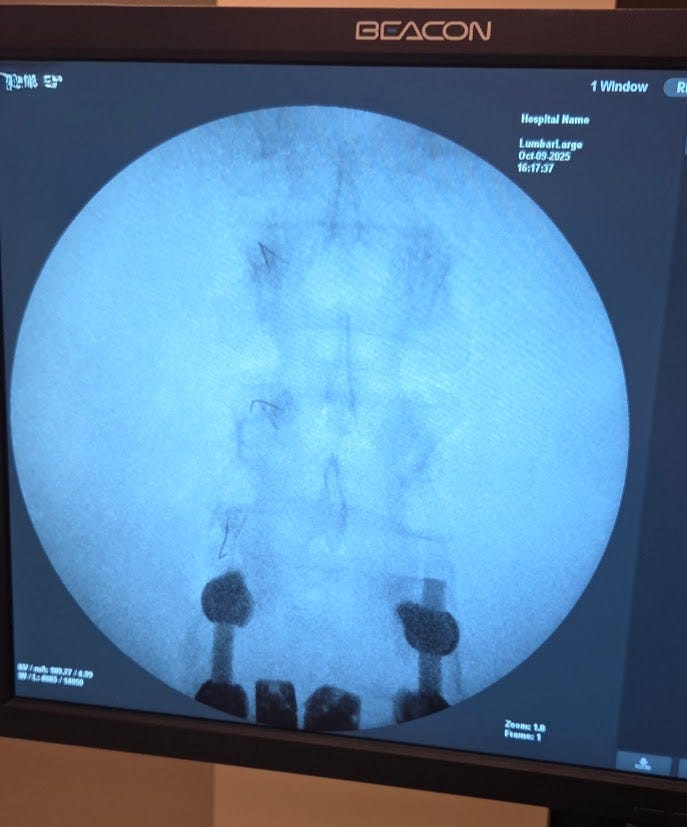

He eventually gave me the name of a spine specialist he trusted. I went to this surgeon. He looked at my MRIs, CAT scan, and X-Rays He pointed out where the Pars was, how it caused the rest of my pelvis and spine to rotate incorrectly (spondylolisthesis). He also showed a bulge, or tear, in my L5 S1. He wanted the list of injuries and surgeries.

I had them written down this time. He looked at the list and shook his head; after a moment, he asked if I was in a safe place. I didn’t understand the question. He said he could operate and fix it by fusing and decompressing the L4 and L5. I didn’t know what this meant; I knew of people who had back surgeries and got better soon after.

She said during the operation, I was on my stomach, and my hands were essentially in straps for the six-hour surgery with all my weight pulling them down.